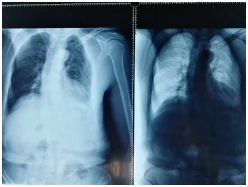

5月21日下午16時(shí)46分,又一位意外受傷患者劉某由輪椅推入我科。據(jù)悉患者因在自家勞作時(shí)從約兩米的高處摔落,患者傷后發(fā)生短暫昏迷,后經(jīng)通知家人急診收入我院骨科,通過(guò)詢問(wèn)病史及完善相關(guān)檢查后,劉某確診為多發(fā)性肋骨骨折及左肩鎖關(guān)節(jié)脫位,應(yīng)盡快予以手術(shù)減輕病痛。在征得患者及家屬同意手術(shù)的情況下,手術(shù)順利完成,患者目前各項(xiàng)生命體征平穩(wěn),現(xiàn)于外科病房接受進(jìn)一步的觀察與治療。